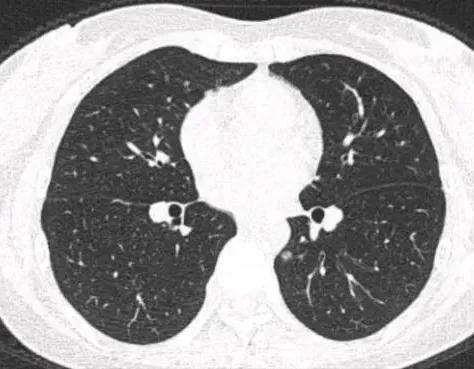

磨玻璃肺结节消融是比手术更好的选择吗?患者消融后反而更焦虑了

肺结节消融治疗作为一种新兴的微创技术,正在改变肺癌患者的治疗选择。然而,这种看似“无痕”的治疗方式,却可能给患者带来意想不到的心理负担。

消融治疗的优势显而易见。与传统手术相比,它具有创伤小、恢复快、并发症少等优点。长沙市中心医院肿瘤科主任王桂华指出:“消融治疗后,已经死亡的结节虽然还在,但在消融治疗的初期因为炎症反应,病灶可能会变大,之后随着炎症反应消退,病灶体积会逐渐缩小,形成空洞或者纤维化等情况。”这种“无痕”的治疗效果,无疑减轻了患者对外观的担忧。

这种焦虑并非空穴来风。消融治疗虽然创伤小,但其治疗效果需要时间来验证。正如王桂华主任所说:“小病灶消融治疗后病变消融彻底,避免开胸手术大动干戈,不影响患者日常生活。”然而,这种“彻底”需要时间来证明,而这段时间恰恰是患者最焦虑的时期。

值得注意的是,消融治疗并非适用于所有肺结节患者。王桂华主任强调:“对于无法耐受外科手术治疗的患者、肺多发结节单纯手术无法完全切除的患者、肺癌术后剩余肺结节手术无法处理的患者可以考虑肺结节消融。”这意味着,在选择治疗方式时,医生需要综合考虑患者的个体差异,而不仅仅是技术的先进性。